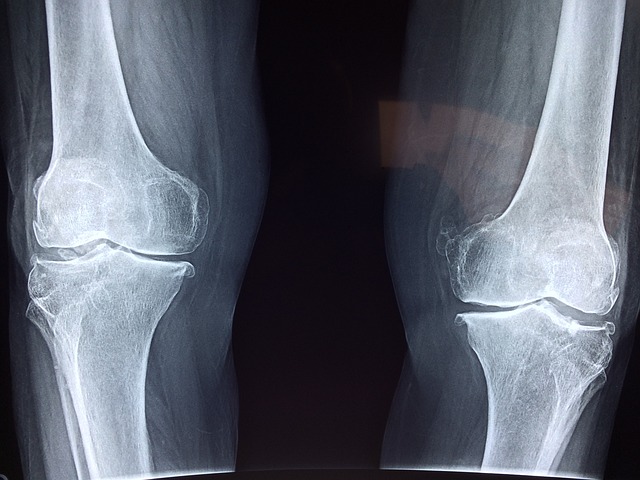

2-1. 관절 및 연골 개선

- 프로테오글리칸의 효능 중 제일 우리 몸에 좋은 효능은 바로 관절과 연골에 많은 개선점을 준다는 것입니다. 프로테오글리칸은 연골 내에서 주고 발견이 되는데 이러한 연골의 유연성과 강도를 유지하는데 큰 역할을 합니다. 만약 프로테오글리칸이 부족하게 된다면 관절염과 연골질환과 같은 다양한 질병에 노출될 수 있기 때문에 반드시 필요한 요소라고 볼 수 있습니다.